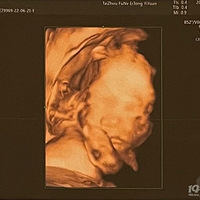

做四维发现胎宝咧嘴笑孕妈认为宝宝健康活泼,医生却紧张了

大奕萌 2022-12-30 14:03

2347 浏览 查看原帖